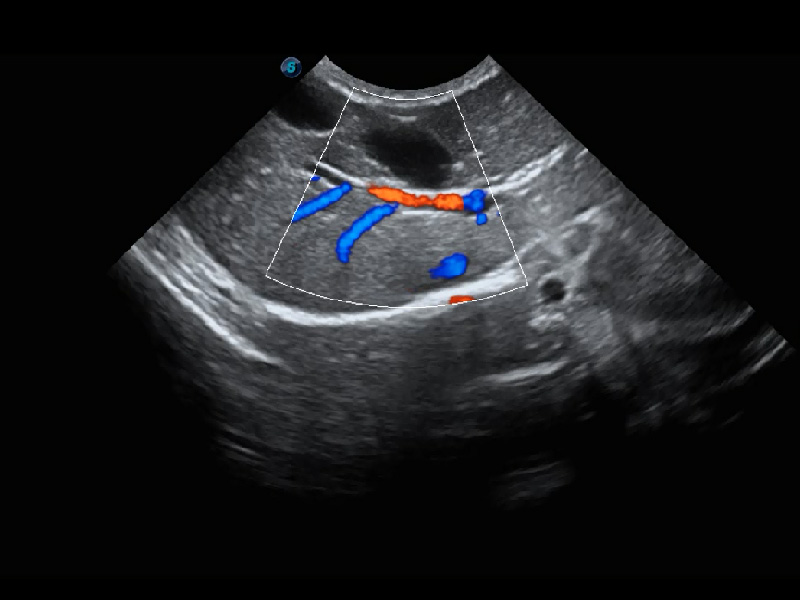

(犬)腎臟血流